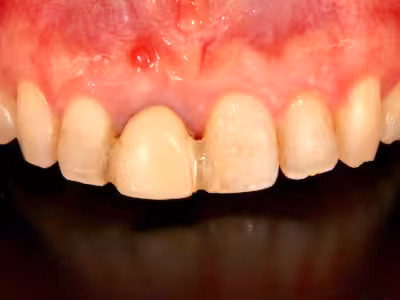

治療前

治療後

40代・女性

来院理由

前歯の治療を他院で行っていたが、これ以上治せないとのことで当クリニックでの治療を希望

治療内容

- ① CT検査・サージガイド作製

- ② 抜歯と同時にインプラント埋入(抜歯即時埋入)

- ③ 結合組織移植

- ④ セラミッククラウン+ラミネートベニア装着

治療期間

約8ヶ月

費用

902,000円(税込・自費診療、保険適応外)

リスク・副作用

- 術後の腫脹・疼痛・出血

- インプラントが骨結合しない可能性

医院コメント

噛む機能だけでなく口元のバランスも改善。

定期メンテナンスにより長期安定を目指します。